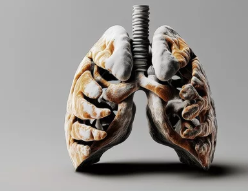

3. 간질성 폐질환의 주요 원인

간질성 폐질환은 다양한 원인으로 발생할 수 있으며, 일부는 원인이 명확하지 않은 경우도 있습니다.

✅ 1) 특발성 폐섬유화증 (IPF, Idiopathic Pulmonary Fibrosis)

- 가장 흔한 원인 (특발성 = 원인 불명)

- 원인을 알 수 없지만, 흡연, 환경적 요인, 유전적 요인 등이 관련됨

- 진행이 빠르며, 치료하지 않으면 생존율이 낮음

✅ 2) 환경적 요인 (유해물질 노출)

- 석탄, 석면, 금속 먼지, 곰팡이 포자, 화학물질(농약, 가스 등)에 장기간 노출될 경우 발생

- 광부, 건설 노동자, 공장 근로자, 농부 등 위험군